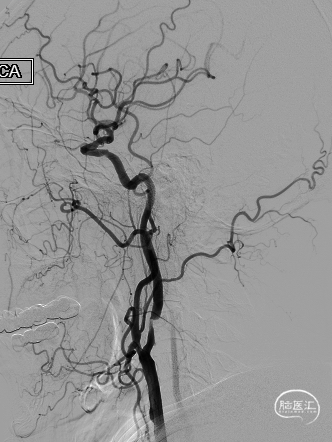

➢ 脑血管造影检查

患者主因言语不利3天入院,头核磁提示右侧额、顶叶多发低灌注梗塞,脑血管造影提示右侧颈内动脉开口重度狭窄,为责任血管,另外患者前交通动脉、右侧后交通动脉开放不良,并且狭窄严重,考虑到高灌注风险,决定分期处理,一期小球囊扩张改善供血,二期支架成型。

扩张完毕后多角度造影显示狭窄较前明显改善(箭头处)。

撤出保护伞观察10分钟复查造影,无弹性回缩,狭窄明显好转,血流明显改善(箭头处),结束手术。